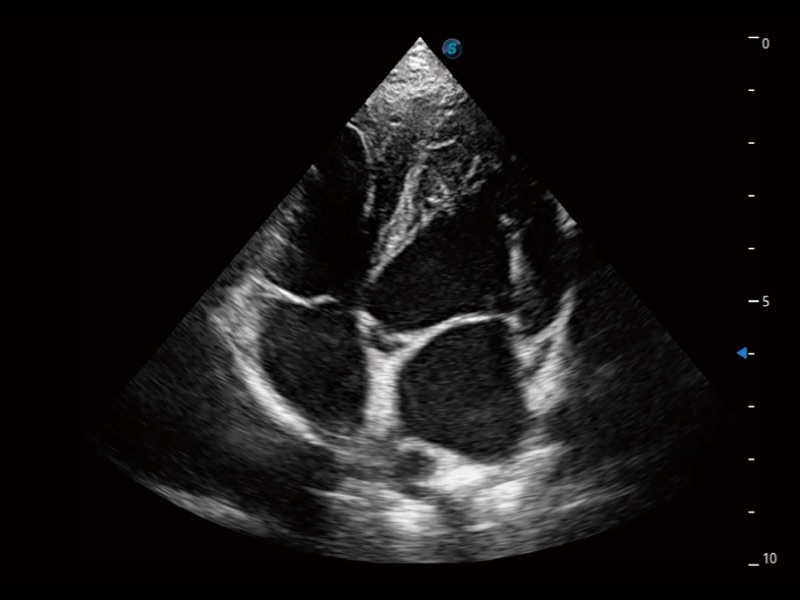

ProPet 70 進(jìn)一步提升了微米成像算法,更加注重對基礎(chǔ)原始圖像的還原和保留,在有效減少斑點(diǎn)噪聲、增強(qiáng)組織邊界顯示的同時(shí),避免過度優(yōu)化丟失真實(shí)的解剖信息。

能夠基于左心室壁追蹤和辛普森法,自動計(jì)算射血分?jǐn)?shù),支持多個(gè)可移動點(diǎn)描跡,與手動測量相比,極大節(jié)省了動物醫(yī)生的時(shí)間和精力。

通過360度任意調(diào)節(jié)3條M型取樣線,在同一心動周期上觀察心臟不同位置的運(yùn)動曲線,得到準(zhǔn)確的心功能測量數(shù)據(jù),有效評估心肌運(yùn)動及左心室功能。

當(dāng)心臟測量結(jié)果超出正常范圍時(shí),可實(shí)時(shí)預(yù)警提示動物醫(yī)生,減少疾病漏診概率。